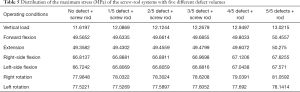

From the data analysis of the stress on the screw-rod system, it can be concluded that with the collapse of the superior endplate of the injured vertebra and the gradual increase in the defect volume of the anterior column, the stress gradually concentrated on the internal fixator (Table 5).

Full table